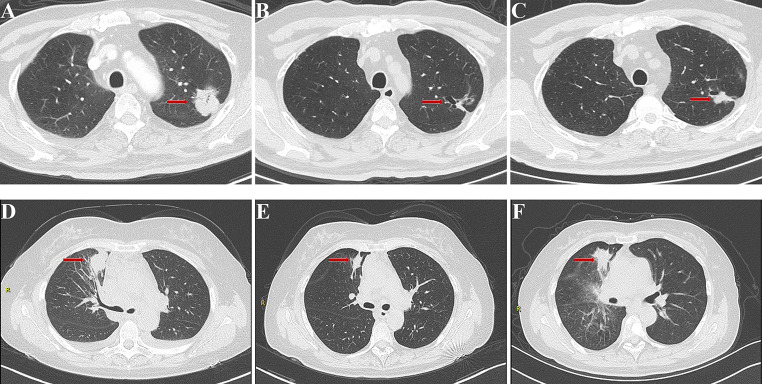

ROC analysis was used to access the predictive performance of the ABC-Score for one-year PFS rate of advanced NSCLC patients treated with icotinib. Results of the analysis showed the following: age (area under the curve (AUC) = 0.573), bone metastases (AUC = 0.615), and CA19-9 (AUC = 0.608). Compared with the three predictors individually, the combined ABC-Score (AUC = 0.660) showed a better predictive accuracy (Fig. 3A). The ABC-Scoring system performed well in the five-fold cross-validation (AUC = 0.623) (Fig. 3B). Kaplan–Meier survival analysis indicated that advanced NSCLC patients in the low ABC-Score group showed better PFS (P < 0.0001) than those in the high ABC-Score group (Fig. 3C). Representative CT images before icotinib treatment, at the time of partial response, and at the time of disease progression in two patients with different ABC-Scores are shown in Fig. 4. The PFS of a 60-year-old woman with an ABC-Score equal to 1 was 17 months, while the PFS of a 57-year-old woman with an ABC-Score of 3 was 8 months.

Fig. 4.

Example of CT images from pre-treatment to progression of two patients with different ABC-Scores. CT images before icotinib treatment (A), at the time of partial response (B), and at the time of disease progression (C) of a 60-year-old woman with the ABC-Score equal to 1. CT images before icotinib treatment (D), at the time of partial response (E), and at the time of disease progression (F) of a 57-year-old woman with the ABC-Score equal to 3